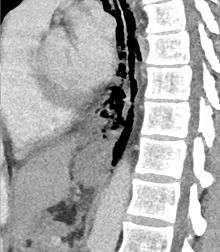

The diagnosis of Boerhaave's syndrome is suggested on the plain chest radiography and confirmed by chest CT scan. The initial plain chest radiograph is almost always abnormal in patients with Boerhaave's syndrome and usually reveals mediastinal or free peritoneal air as the initial radiologic manifestation. With cervical esophageal perforations, plain films of the neck show air in the soft tissues of the prevertebral space.

Hours to days later, pleural effusion(s) with or without pneumothorax, widened mediastinum, and subcutaneous emphysema are typically seen. CT scan may show esophageal wall edema and thickening, extraesophageal air, periesophageal fluid with or without gas bubbles, mediastinal widening, and air and fluid in the pleural spaces, retroperitoneum or lesser sac.

The most common anatomical location of the tear in Boerhaave syndrome is at left posterolateral wall of the lower third of the esophagus, 2–3 cm before the stomach.[8]